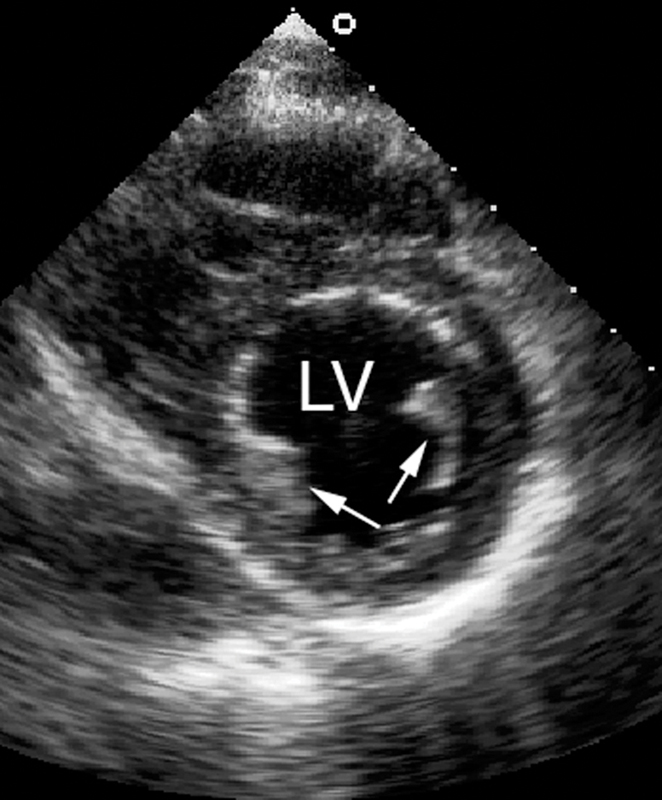

فحوصات تشخيصية لبعض امراض القلب والشرايين التاجية